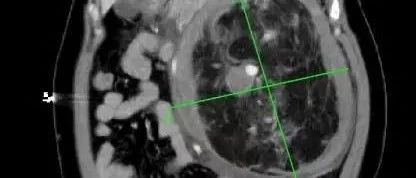

前一段時間,家住惠城區(qū)的林女士(化名)突發(fā)腹痛嘔吐,由120送至惠州市第三人民醫(yī)院急診科。完善全腹部CT后,醫(yī)生發(fā)現(xiàn)患者左腎存在一個巨大腫瘤,直徑約20cm,并伴有破裂出血。

左腎巨大腎錯構瘤約20*20*13cm

經過激烈討論,岳峰主任指出,林女士腫瘤體積巨大,且有破裂出血、周圍滲出較多,盆腔、腹腔積血等情況,腫瘤組織脆弱,周圍結構呈板狀,混雜無界限,手術難度極大,最保險的手術方案就是完整切除整個腎臟。考慮到林女士才四十多歲的年紀以及家屬的期盼,大家決定行左腎部分切除術,完整切除左腎巨大腫瘤,但這一方案,醫(yī)護團隊將要承擔極大的風險!

開刀后,腹腔全是血,醫(yī)生迅速把血吸干凈,找到出血位置。只見腫瘤與腹主動脈、腸系膜血管包括腎臟粘連在一起。損傷后極易出血,必須逐一結扎后才能推進腫瘤切除。然而,腫瘤實在太大了,嚴重遮擋視野,出血難以避免,止血十分困難!岳峰主任指示,我們要以最快速度結束戰(zhàn)斗!

隨著超聲檢查在體檢中普及,超過一半的偶發(fā)腎錯構瘤在體檢中被發(fā)現(xiàn),隨后經CT或MRI確診。比如林女士,她的腹部增強CT中可見明顯強化的血管結構和無強化的脂肪組織。